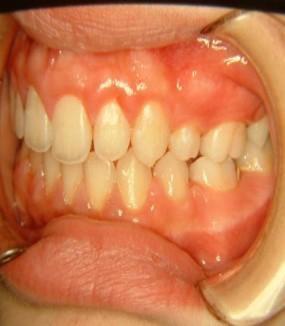

Όταν υπάρχει γενετική έλλειψη μονίμων δοντιών αν επέμβουμε ορθοδοντικά σε μικρή ηλικία κλείνουμε τα κενά μικραίνοντας τα οδοντικά τόξα και έτσι το παιδί αποφεύγει μελλοντικές προσθέσεις (γέφυρες ή εμφυτεύματα).

Γενετικώς ελλείποντα δόντια (ο άνω αριστερός πλάγιος, ο άνω δεξιός 2ος προγόμφιος, οι κάτω δεύτεροι προγόμφιοι αμφοτερόπλευρα.)

Μετά το πέρας της ορθοδοντικής θεραπείας, (2η φωτογραφία), τα κενά που δημιουργήθηκαν

από την έλλειψη των μονίμων δοντιών μετά την φυσιολογική απόπτωση των νεογιλών δοντιών, έκλεισαν με ορθοδοντική παρέμβαση